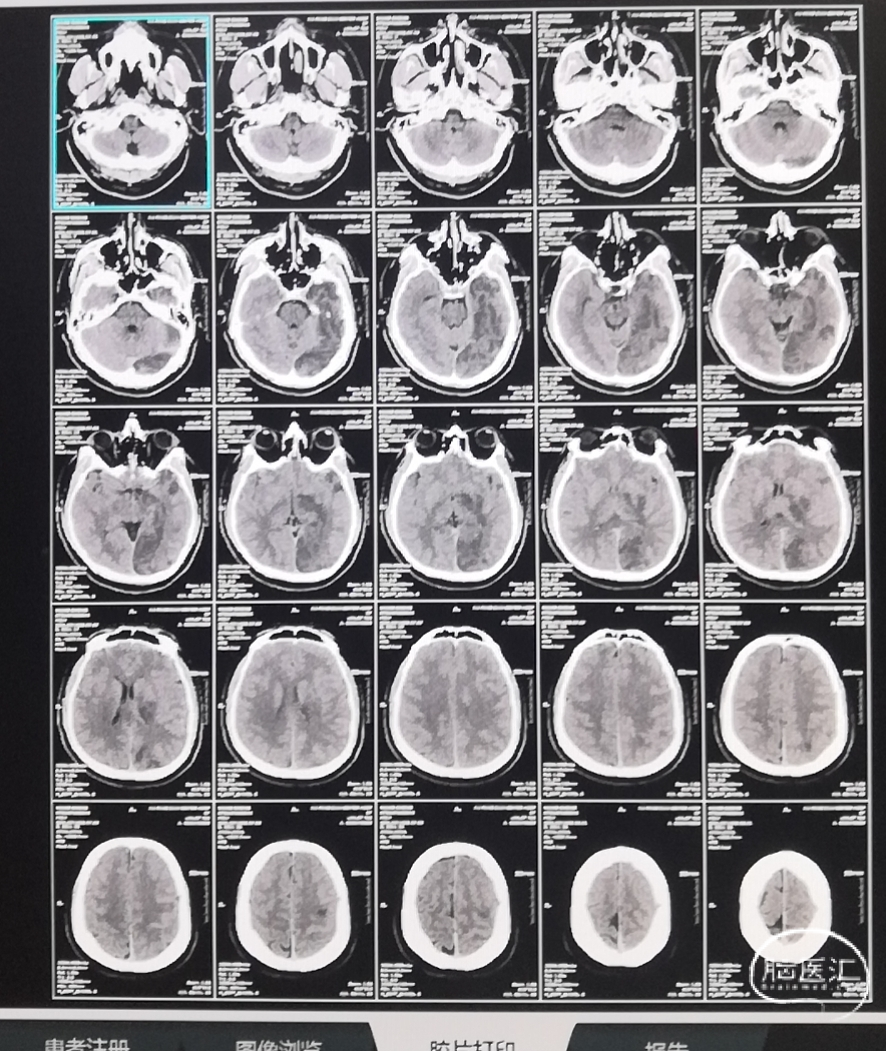

病人神志清,双眼左侧凝视恢复,失语,右侧肢体二级,左侧肢体肌力全部恢复。

1. 梗死灶出现与术前DWI影像一致

2. 鞍上池及环池清晰

3. 左额顶叶皮层及半卵圆中心区没有梗塞

术后十天复查头部CT影像

年轻患者,血管代偿好,积极取栓治疗,是病人恢复保证。通桥银蛇®颅内支持导管的到位性能为整个手术提供巨大支持。